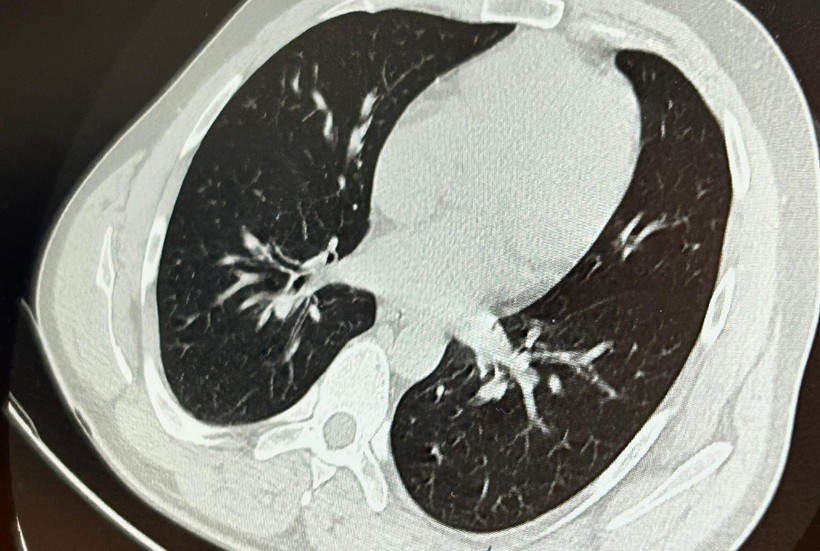

Göğüs Cerrahisi uzmanları Dr. Sadullah Aksoy ve Dr. Beniz İrem Ersoy Şığva tarafından hastaya bronkoskopi işlemi uygulandı. İmplant vidası, sol akciğerin üst lobunda saplanmış şekilde bulundu.

Vidanın bulunduğu konum nedeniyle güçlükle yerinden oynatılabildi. Ancak, yapılan tüm müdahalelere rağmen vide yerinden çıkarılamadı.

Aynı gün hastamızı hazırladık. Bronkoskopi sırasında, implant vidasının sol üst lobun anterior segment bronşuna saplanmış pozisyonda olduğunu gördük. Üroloji bölümünde taş çıkarma işlemlerinde kullanılan cihazla müdahale ettik. İlk denemede implant tamamen çıkarılamadı ancak yerinden oynatılabildi. Bunun üzerine bir süre bekleyip hastayı yeniden bronkoskopi için hazırlamaya başladık. İşlem yaklaşık 3,5-4 saat sürdü ve saat 18.30 civarında hasta işlemden çıkarıldı."

Daha sonra hasta için yeniden bronkoskopi planladıklarını ancak bu süreçte hastanın şiddetli bir öksürük geçirdiğini aktaran Aksoy, "Şiddetli öksürük sonrası yapılan kontrol akciğer filminde implant vidası görünmedi. Bunun üzerine toraks ve batın BT (bilgisayarlı tomografi) görüntülemesi istedik. Sonuçlarda implantın akciğerden çıktığı ve vücutta herhangi bir yerde bulunmadığı tespit edildi" dedi.